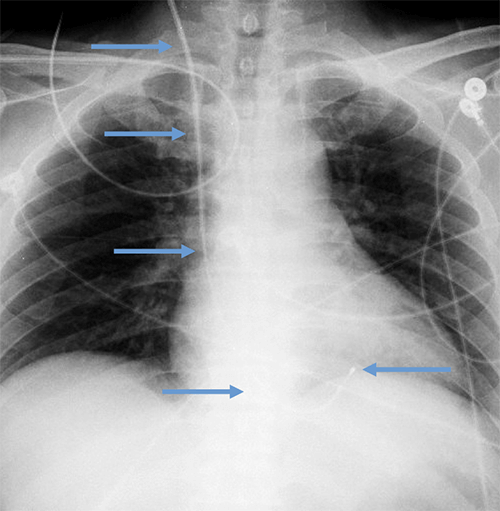

- CEID images with lead types:

Pacemaker with transvenous leads